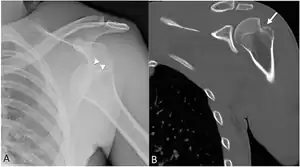

| Anterior shoulder dislocation on X-ray with a large Hill–Sachs lesion | |

Diagnosis can be suspected by history and physical examination which is usually followed by imaging. Because of the mechanism of injury, apprehension of anterior dislocation is common with provocative maneuvers. Hill–Sachs lesions have been classified as "engaging" or "non-engaging", with engaging lesions defined by the ability of the glenoid to sublux into the humeral head defect during abduction and external rotation. Engaging dislocations have a higher risk of recurrent anterior dislocation, and their presence can help guide surgical management.[2] Imaging diagnosis conventionally begins with plain film radiography. Generally, anteroposterior (AP) radiographs of the shoulder with the arm in internal rotation offer the best yield while axillary views and AP radiographs with external rotation tend to obscure the defect. However, pain and tenderness in the injured joint make appropriate positioning difficult and in a recent study of plain film x-ray for Hill–Sachs lesions, the sensitivity was only about 20%. i.e. the finding was not visible on plain film x-ray about 80% of the time.[3]

X-ray at left shows anterior dislocation in a young man after trying to get up from his bed. X-ray at right shows same shoulder after reduction and internal rotation, revealing both a Bankart lesion and a Hill-Sachs lesion.